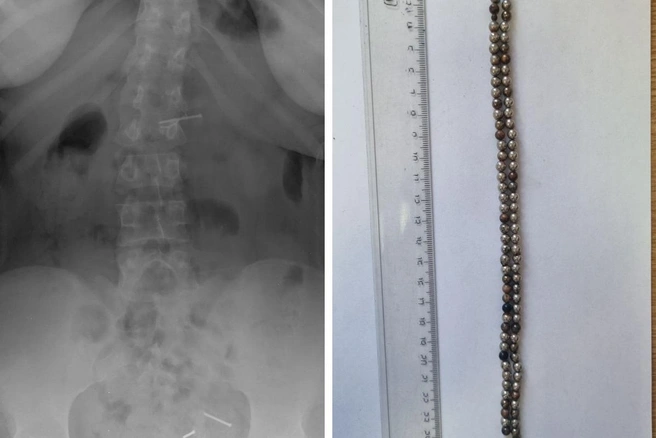

«Обследование выявило множественные рентгенконтрастные предметы в кишечнике и явные признаки кишечной непроходимости. В ходе экстренной операции было удалено 25 магнитов», — поделилась специалист.

Уточняется, что магниты могут притянутся через стенки кишечника, вызывая непроходимость, некроз, перфорацию и образование свищей. Выяснилось, что 25 магнитов находились уже длительное время в организме ребенка, что привело к серьезным последствиям. Однако операция прошла успешно, и сейчас его жизни ничего не угрожает.